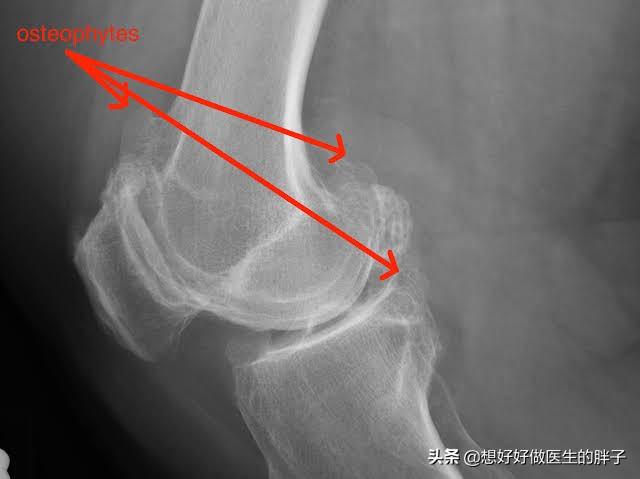

为什么有的人将骨赘称之为骨刺呢?就是因为有一些骨赘是突出骨骼范围之外的,其实这些骨赘比较小的时候,是不会对周边的软组织产生刺激和损伤的,但是如果当骨刺比较大以后,就有可能影响到周边的软组织、肌腱以及骨结构,从而产生疼痛、肿胀以及屈伸受限等症状。(下图的膝关节x线,患者就可能产生屈伸障碍、关节后方的疼痛或不适)

看到这里相信大家应该明白了,骨赘(骨刺、骨质增生)本来是帮忙的,之所以形成骨赘的基础是关节软骨的磨损,早期同时存在着纤维软骨修复、骨赘增生;晚期出现软骨的彻底破坏,表现为软骨硬化、软骨消失及软骨下局灶性骨坏死。晚期会导致严重的间隙狭窄和疼痛,需要手术解决大关节的问题。